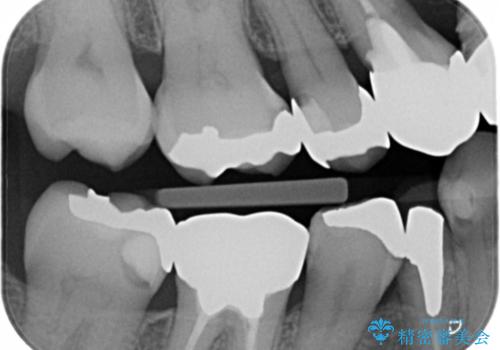

- メタルインレーやりかえ希望の患者様です。

拡大鏡下でメタル、う蝕の除去を行いe-maxインレー(セラミックインレー)で治療しました。

適合の良いe-maxインレーが入りました。

銀の詰め物に比べてセラミックインレーは虫歯の再発のリスクが少なくなります。